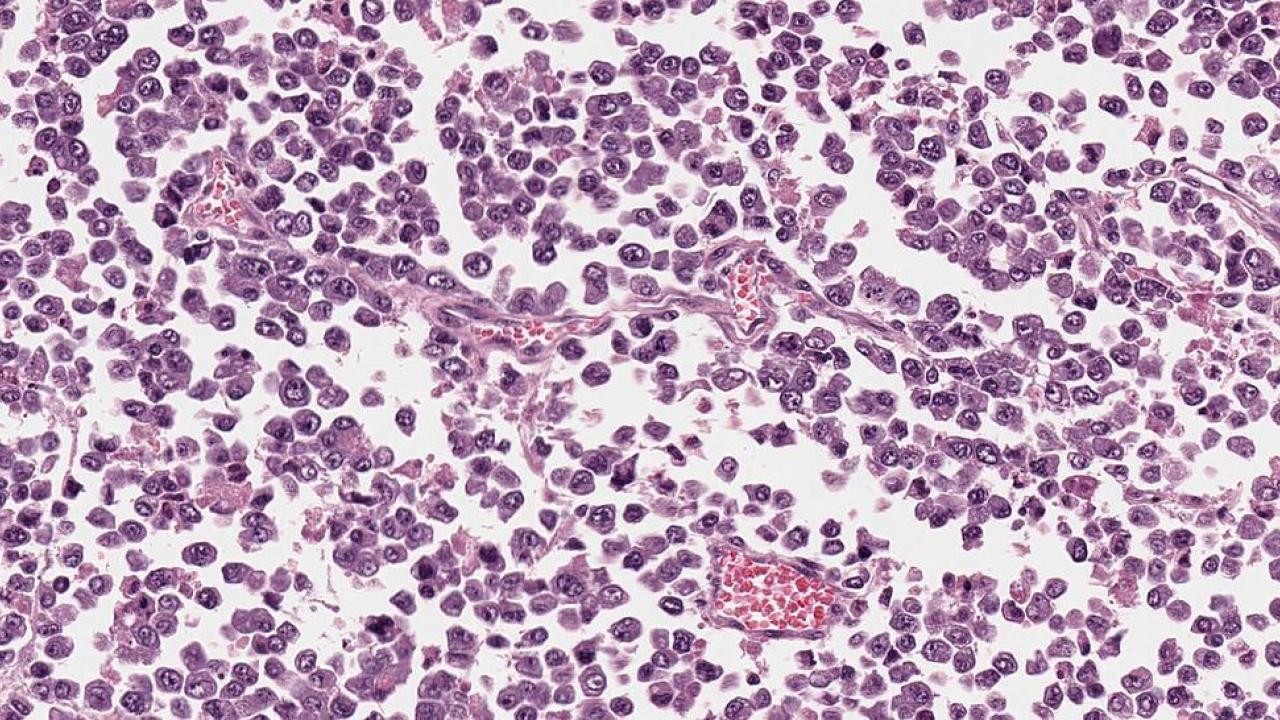

Soft Tissues: Alveolar Rhabdomyosarcoma

Alveolar Rhabdomyosarcoma, Magnification 20. Dyshesive And Infiltrative

rhabdomyosarcoma alveolar infiltrative magnification

Webpathology.com: A Collection Of Surgical Pathology Images

rhabdomyosarcoma alveolar webpathology pathology

Webpathology.com: A Collection Of Surgical Pathology Images

rhabdomyosarcoma alveolar webpathology pathology comments microscopic

Alveolar Rhabdomyosarcoma | Basicmedical Key

alveolar rhabdomyosarcoma composed preservation tumor cellular cells peripheral round